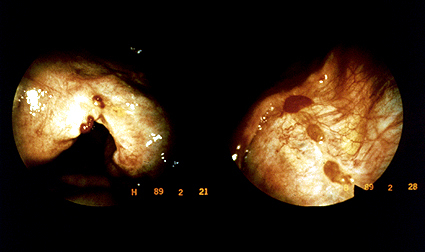

scrotal angiokeratoma

>40 years

Usually symptomless but can bleed